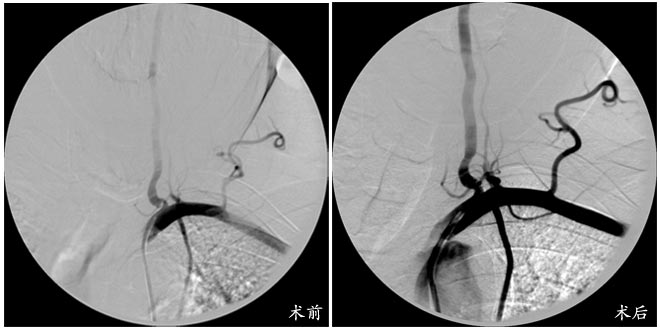

近日,我院神经外科为一名57岁老年男性重度左椎动脉起始段狭窄患者独立完成了血管内介入支架置入手术获得成功,病人的一过性黑朦、失语、头痛、头晕等脑缺血症状完全消失。头颈血管内介入支架置入手术难度大,风险高,过去只有部分三级医院神经外科能完成此类手术,此例手术的成功开展,填补了我院该医学领域的空白,标志着我院神经外科的业务领域又有了新的突破。经过神经外科医护人员的精心治疗与护理,患者恢复良好,已康复出院。